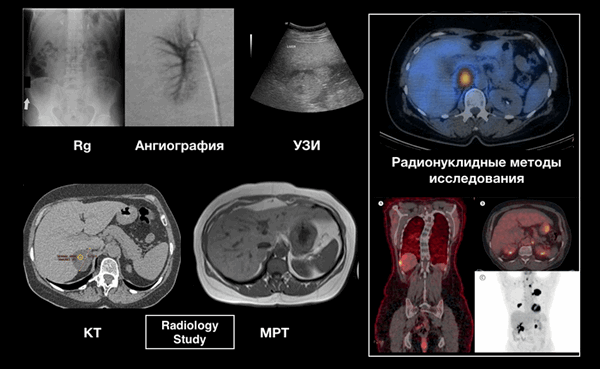

Методы исследования

![]()

Методы исследования:

Основными методами исследования являются КТ и МРТ.

На рентгенограмме возможно визуализировать надпочечники с кальцификацией.

Ангиографию используют для заборы крови из вены надпочечников, чтобы разрешить вопрос при двухстороннем поражении о том какая из аденом функционирующая.

УЗИ не является методом выбора для диагностики инциденталом надпочечников, но позволяет выполнять тонкоигольную биопсию под контролем УЗИ.

ОФЭКТ/КТ позволяет достоверно говорить об этиологии при размере образования от 2 см.

ПЭТ/КТ используется у пациентов в анамнезе, которых есть рак для поиска метастазов.